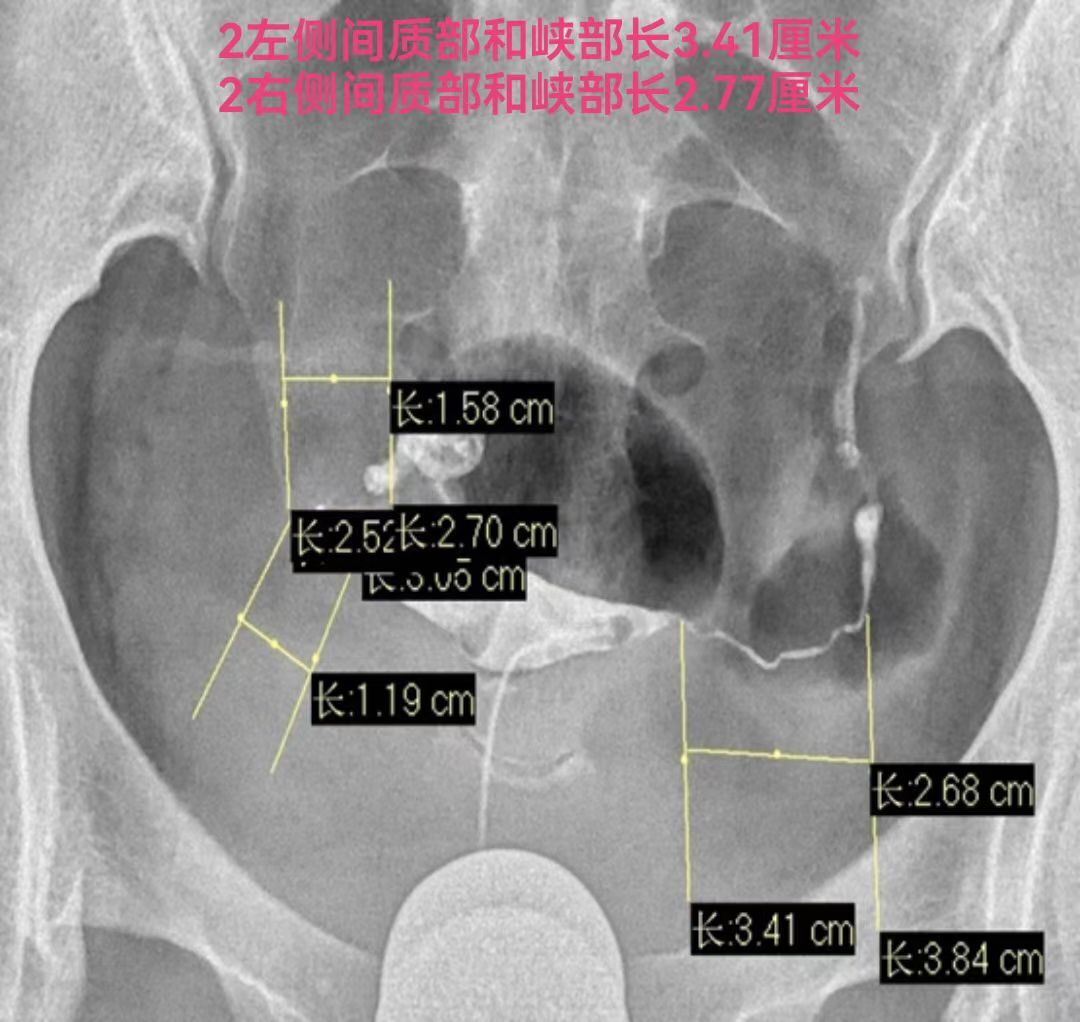

输卵管间质部长约1cm,管腔狭窄,直径0.5-1mm。峡部在间质部外侧,长约2-3cm,直径约0.2-2mm。输卵管间质部和峡部的管腔是输卵管最细的部位,是最适合的栓塞的部位,输卵管间质部和峡部的总长度也就3-4厘米。输卵管栓塞铂金弹簧圈最常用的是2-2(长2厘米,两端直径都是2毫米)或3-2(长2厘米,一端直径小2毫米另一端直径大是3毫米,就是向宝塔一样,有时被称为塔圈)。一般栓塞一枚弹簧圈可以完全栓塞间质部和峡部的输卵管管腔,而且一枚2厘米长的弹簧圈的两端由于弹性回缩力的回缩,像哑铃一样两端较粗大,可以卡在输卵管内壁上,完全封闭管腔,所以栓塞一枚弹簧圈栓塞最牢固。就像红酒瓶塞一个塞子的最紧实,只有栓塞位置不好才补栓多一个串联的弹簧圈。

因此致密栓塞不仅是多花钱多受罪,而且还没有栓塞一个合适的弹簧圈栓塞的严实。请看下图双侧输卵管积水两侧输卵管各栓塞一个弹簧圈的术前术后标识。